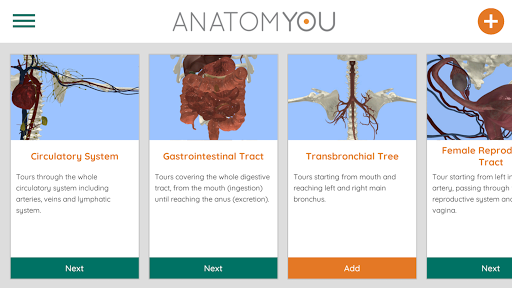

باستخدام الواقع الافتراضي ، سوف تكون قادرًا على التنقل على طول الهياكل التشريحية ، لتصبح جزءًا من علم التشريح البشري: الجهاز الدوري ، والجهاز التنفسي ، والجهاز الهضمي ، والبولي ، الدموي ، والإناث.

يوفر الوصول المجاني لبعض طرق الملاحة في أي من الأنظمة المذكورة تقريبًا. يتم تقديم محتوى إضافي يمكن شراؤه في قسم متجر التطبيقات داخل التطبيق.

هذه نسخة تم تجديدها حديثا من Anatomyou VR. وتشمل الميزات: - تشريح الإنسان أكثر واقعية ، وتعزيز النماذج والقوام. - تفاعل أفضل للمستخدم في أوضاع الواقع الافتراضي والشاشة الكاملة. - القوائم والصور المجددة تماما يوفر الملاحة بديهية. - محتوى سريري إضافي التحقق من صحة من قبل خبرائنا. - يجب على المستخدمين السابقين قبول بعض الأذونات (GoogleVR SDK). لقد بذلنا الكثير من الجهد في هذه الترقية ، آمل أن تستمتع بها!